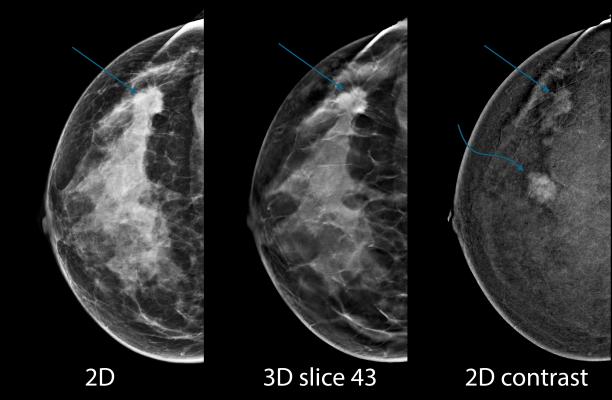

Upstate Offers 3 D Guided Biopsy To Increase Accuracy Patient